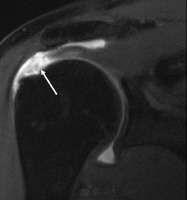

MRI

Magnetic resonance imaging (MRI) and ultrasound[27] are comparable in efficacy and helpful in diagnosis although both have a false positive rate of 15 - 20%.[28] MRI can reliably detect most full-thickness tears although very small pinpoint tears may be missed. In such situations, an MRI combined with an injection of contrast material, an MR-arthrogram, may help to confirm the diagnosis. It should be realized that a normal MRI cannot fully rule out a small tear (a false negative) while partial-thickness tears are not as reliably detected.[29] While MRI is sensitive in identifying tendon degeneration (tendinopathy), it may not reliably distinguish between a degenerative tendon and a partially torn tendon. Again, magnetic resonance arthrography can improve the differentiation.[29] An overall sensitivity of 91% (9% false negative rate) has been reported indicating that magnetic resonance arthrography is reliable in the detection of partial-thickness rotator cuff tears.[29] However, its routine use is not advised, since it involves entering the joint with a needle with potential risk of infection. Consequently, the test is reserved for cases in which the diagnosis remains unclear.

Diagnostic modalities, dependent on circumstances, include X-ray, MRI, MR arthrography, double-contrast arthrography, and ultrasound. Although MR arthrography is currently considered the gold standard, ultrasound may be most cost-effective.[16] Usually, a tear will be undetected by X-ray, although bone spurs, which can impinge upon the rotator cuff tendons, may be visible.[17] Such spurs suggest chronic severe rotator cuff disease. Double-contrast arthrography involves injecting contrast dye into the shoulder joint to detect leakage out of the injured rotator cuff[18] and its value is influenced by the experience of the operator. The most common diagnostic tool is magnetic resonance imaging (MRI), which can sometimes indicate the size of the tear, as well as its location within the tendon. Furthermore, MRI enables the detection or exclusion of complete rotator cuff tears with reasonable accuracy and is also suitable to diagnose other pathologies of the shoulder joint.[19]